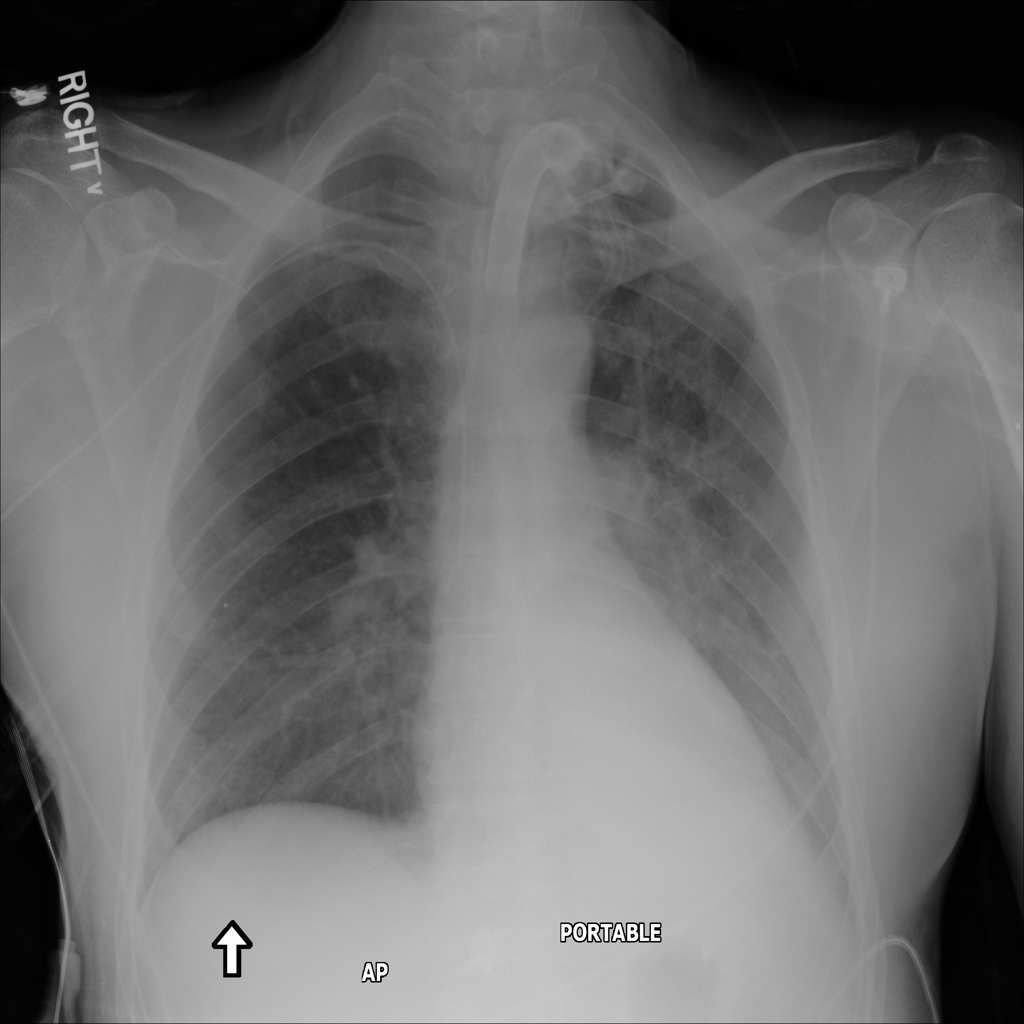

PAT-C1A7 · IMG-055Consolidation

PAT-C1A7 · IMG-055

AP